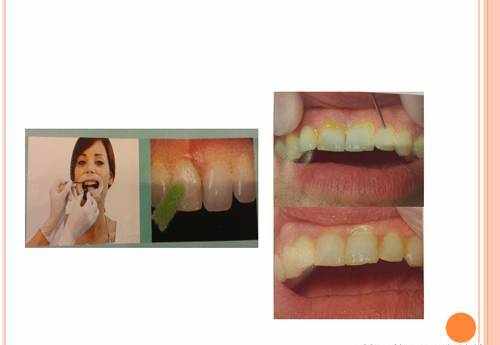

通过涂氟保护漆,让出现了脱矿的牙齿(早期蛀牙的表现)得到了明显的修复。